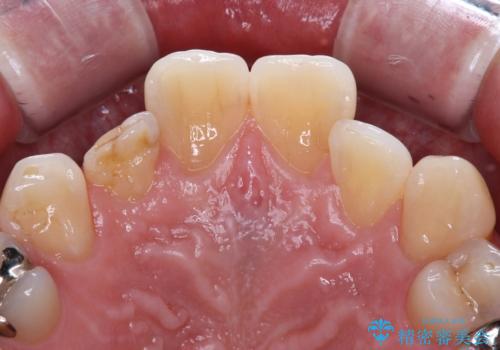

- 内側に倒れている前歯が擦れてしみるとのことで来院された患者様です。

削れていた部分は詰め物が入っていましたが、縁の部分がしみているようで、変色も目立っていたため、オールセラミッククラウンにて補綴治療を行うこととしました。